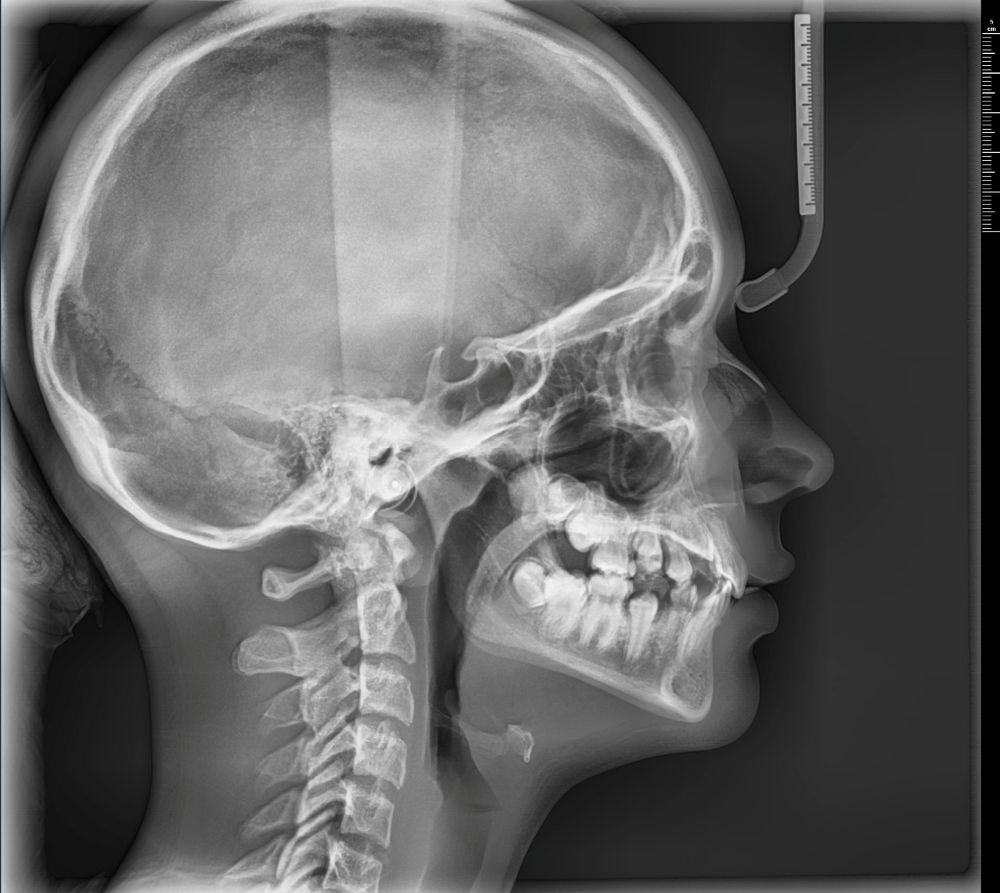

- wyraźne obrazy 2D i 3D — pomocne przy implantach, ósemkach, leczeniu kanałowym i ortodoncji

Pantomogram pokazuje cały stan uzębienia i kości — dzięki temu można wykryć zmiany, których nie widać na małym zdjęciu punktowym (jak torbiele, stany zapalne czy problemy ze stawami). To proste badanie, które warto wykonać profilaktycznie co kilka lat.